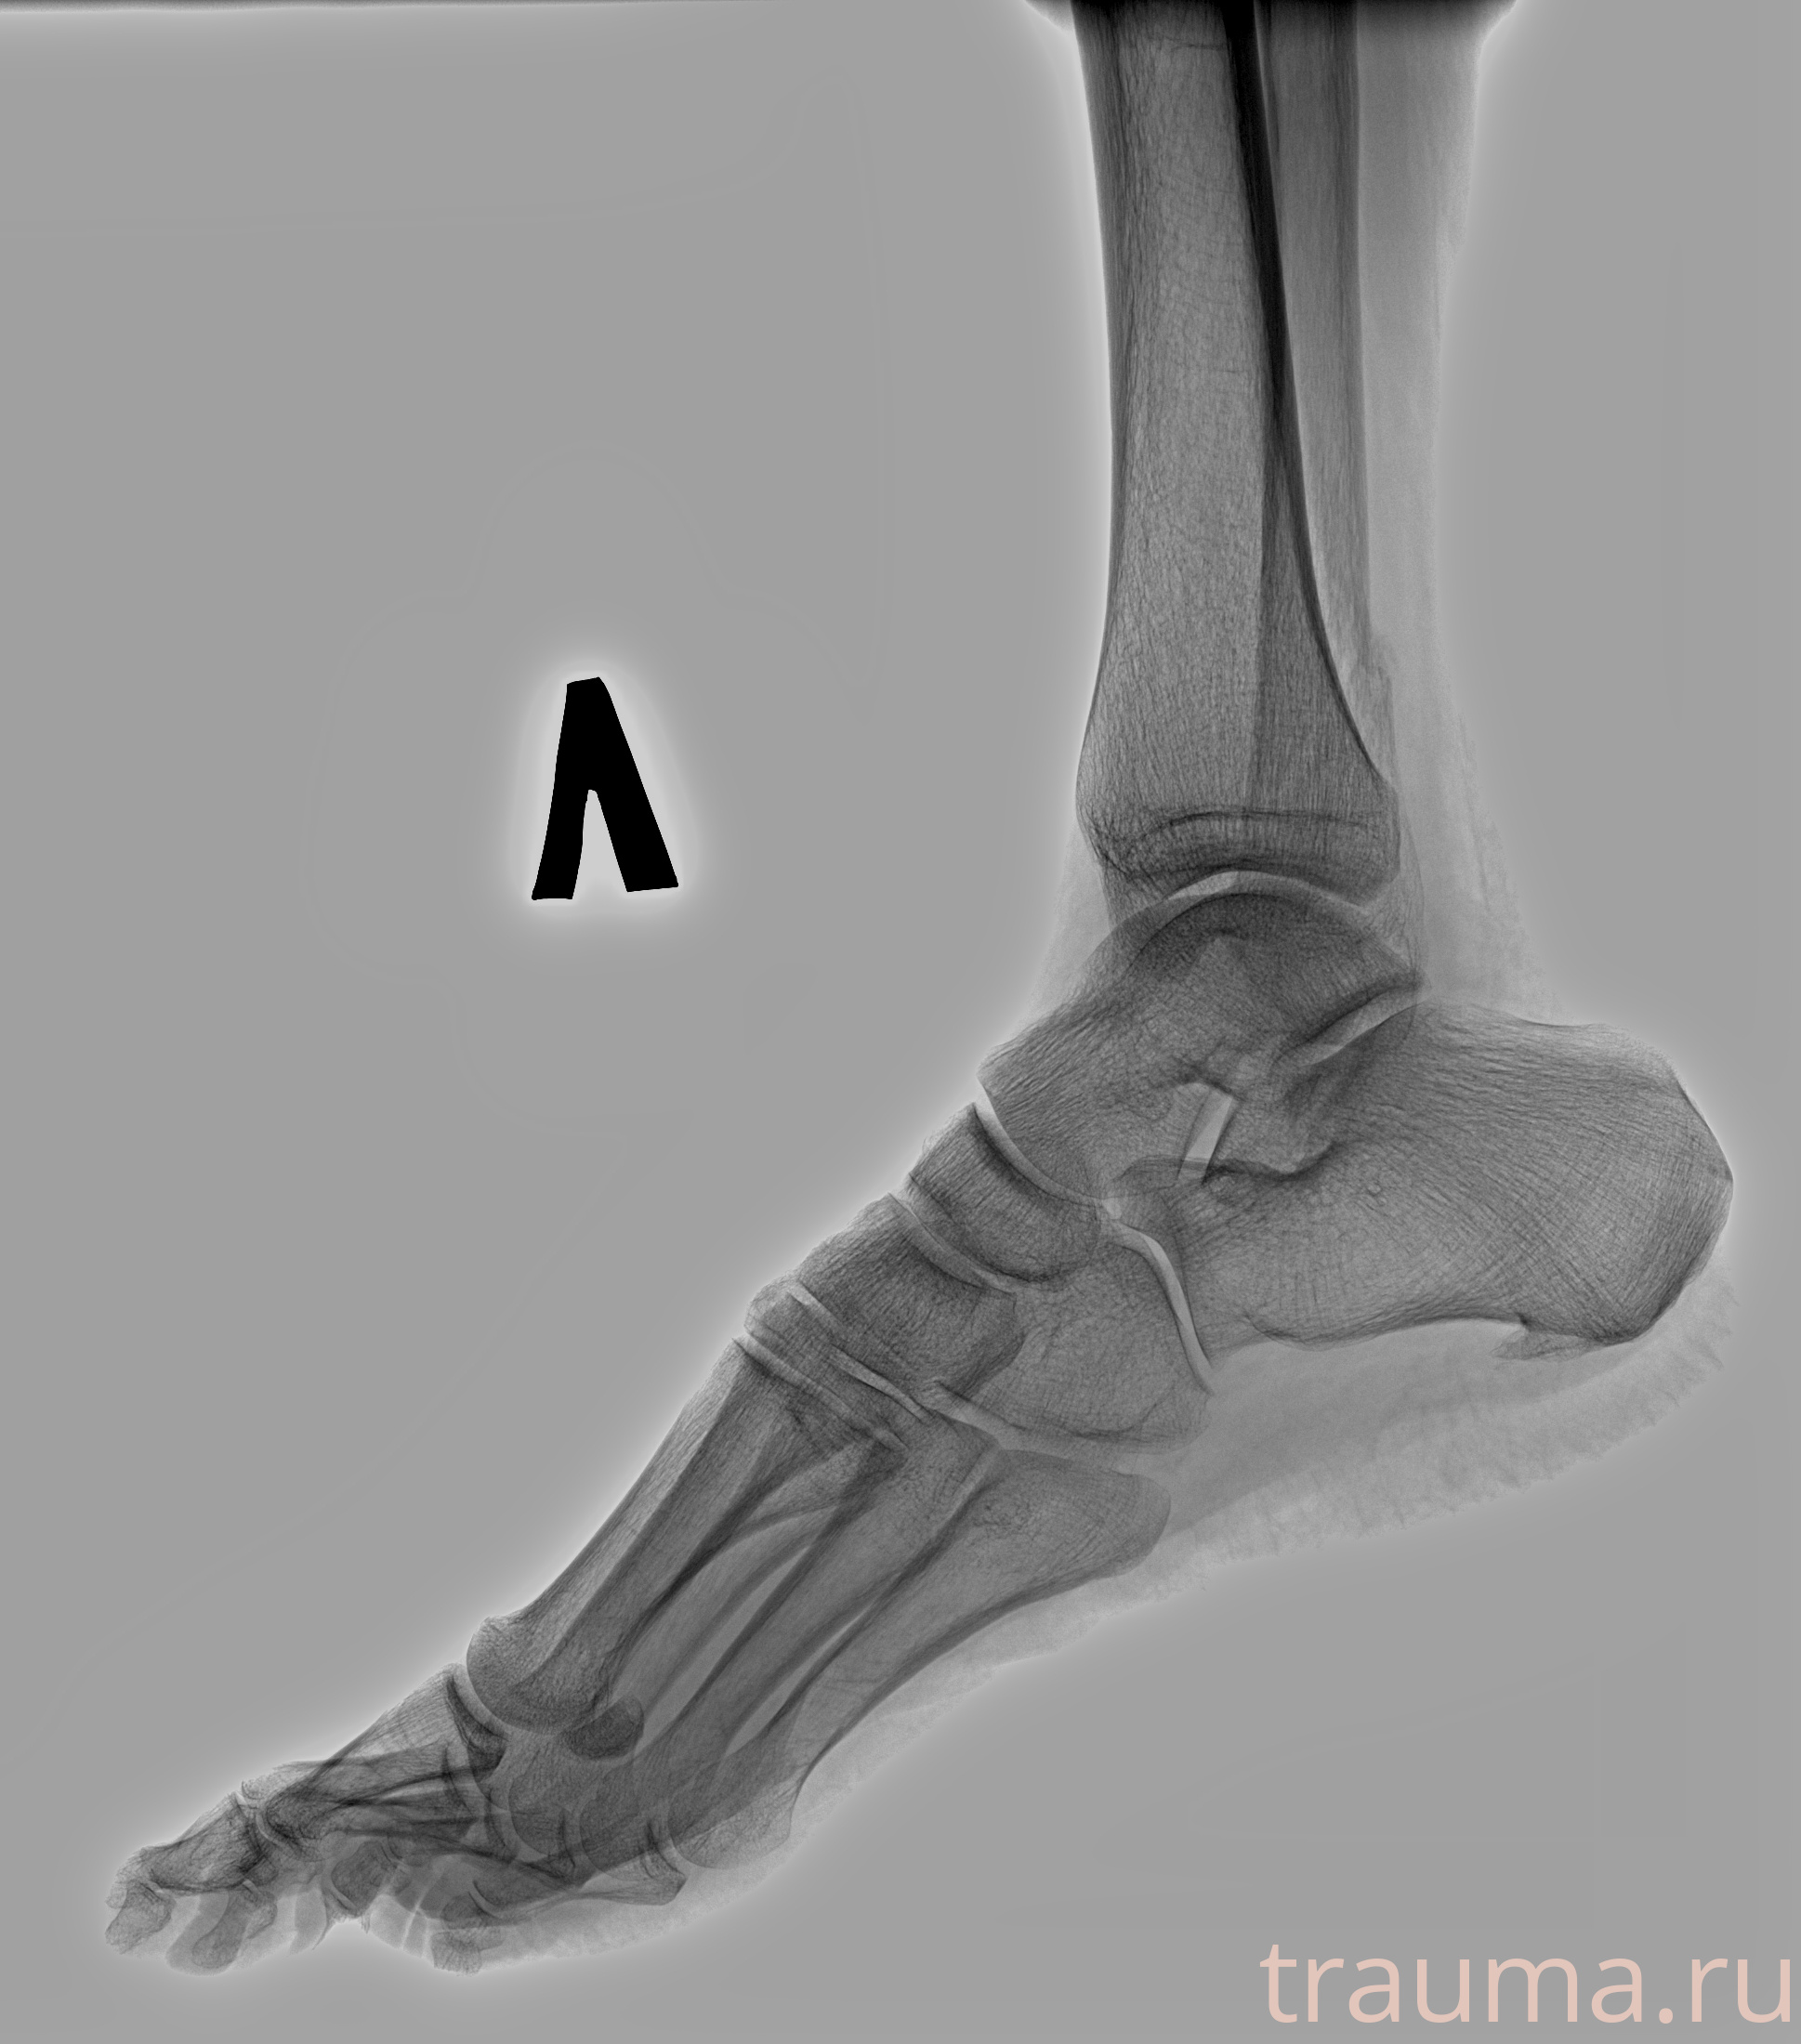

Рентгенограммы

Рентген на дому: по вашему адресу приезжает врач-рентгенолог, травматолог-ортопед с мобильным рентгеновским аппаратом, проводит диагностику травмы или заболевания, делает необходимые рентгенограммы, дает рекомендации по дальнейшему лечению. Получить качественные снимки в домашних условиях возможно благодаря уникальной методике, разработанной МосРентген Центром для института  Склифосовского

Яркость: 1   Контраст: 1   Инвертировать: 0 Увеличение: 1

Перетаскивайте мышь вверх/вниз для контраста, влево/право для яркости. Прокрутка колесом изменяет масштаб. Нажмите Сбросить для возврата к исходному изображению. При увеличении держите мышь в той области, которую хотите рассмотреть.